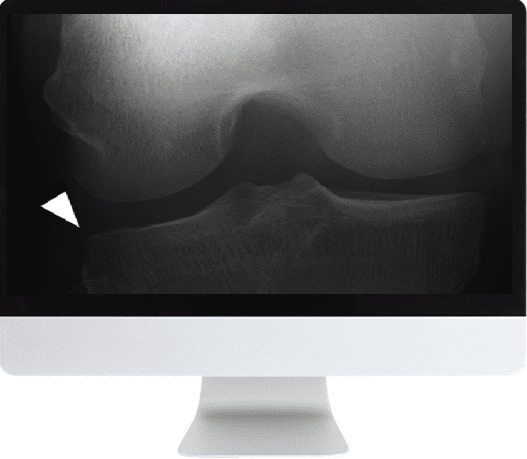

Musculoskeletal Imaging for the Practicing Radiologist 2018 (ARRS VIDEOS) (CME VIDEOS) is a comprehensive course designed to provide radiologists in broad practice settings with practical, step-by-step guidance on diagnosing and managing common musculoskeletal conditions. This course offers detailed coverage of key musculoskeletal anatomy and pathology, imaging techniques, and interpretive strategies to strengthen clinical expertise.

This course includes a series of structured modules covering essential topics in musculoskeletal imaging, presented by expert faculty. Participants will follow a clear educational progression through anatomy, pathology, imaging techniques, and diagnostic challenges.

• Ligamentous Injuries of the Knee: Analysis of MRI Footprints — D. Resnick

• Meniscal Lesions in the Knee: Basics and Beyond — C. Chung